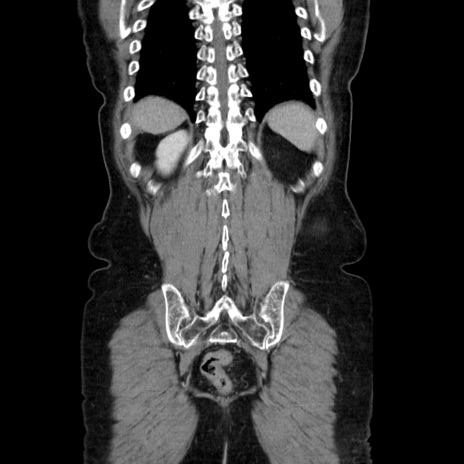

症例5(冠状断像)

【症例】70歳代女性

【主訴】お腹が張る

【現病歴】1週間くらい前から腹部膨満の自覚あり。昨日夜から増悪したため、本日救急外来受診。

【身体所見】意識清明、BT 36.5℃、BP 165/106mmHg、HR 80bpm、SpO2 98%、腹部:膨満、軟、自発痛・圧痛なし、触診にて不快感あり、腸蠕動音:減弱

【データ】WBC 12600、CRP 1.04